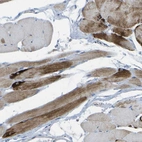

Immunohistochemical staining of human pancreas shows moderate cytoplasmic positivity in exocrine glandular cells and weak cytoplasmic positivity in endocrine glandular cells.